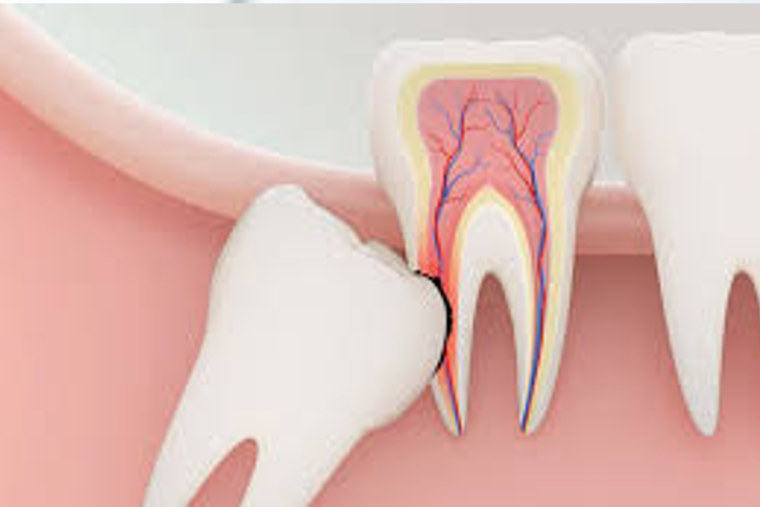

Endondontzia

Hortzeriak zati batzuk ezkutuan ditu, zaindu ikusten ez dena.

- Desbitalizazioa